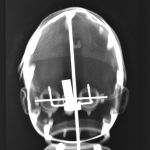

Distanced from the actual procedures (at the time) I was able to study these images for what they were. The half-familiar and recognizable bony structures, barium meal enemas, brain and body scans which became mingled with my X-rays of exotic flowers, fruit and vegetables (dipped in barium meal) plus dolls limbs and heads.

Similarities were seen between a pepper and a text book heart, a bundle of parsley and cerebral blood vessels. Dislocated dolls heads and limbs became floating body parts.